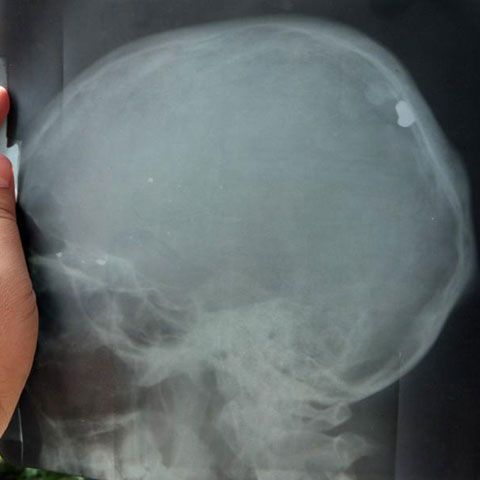

26 sept. 2009, 16:57Ultimele StiriBărbatul împuşcat în cap de politişti, la Brăila, are şanse minime de supravieţuire